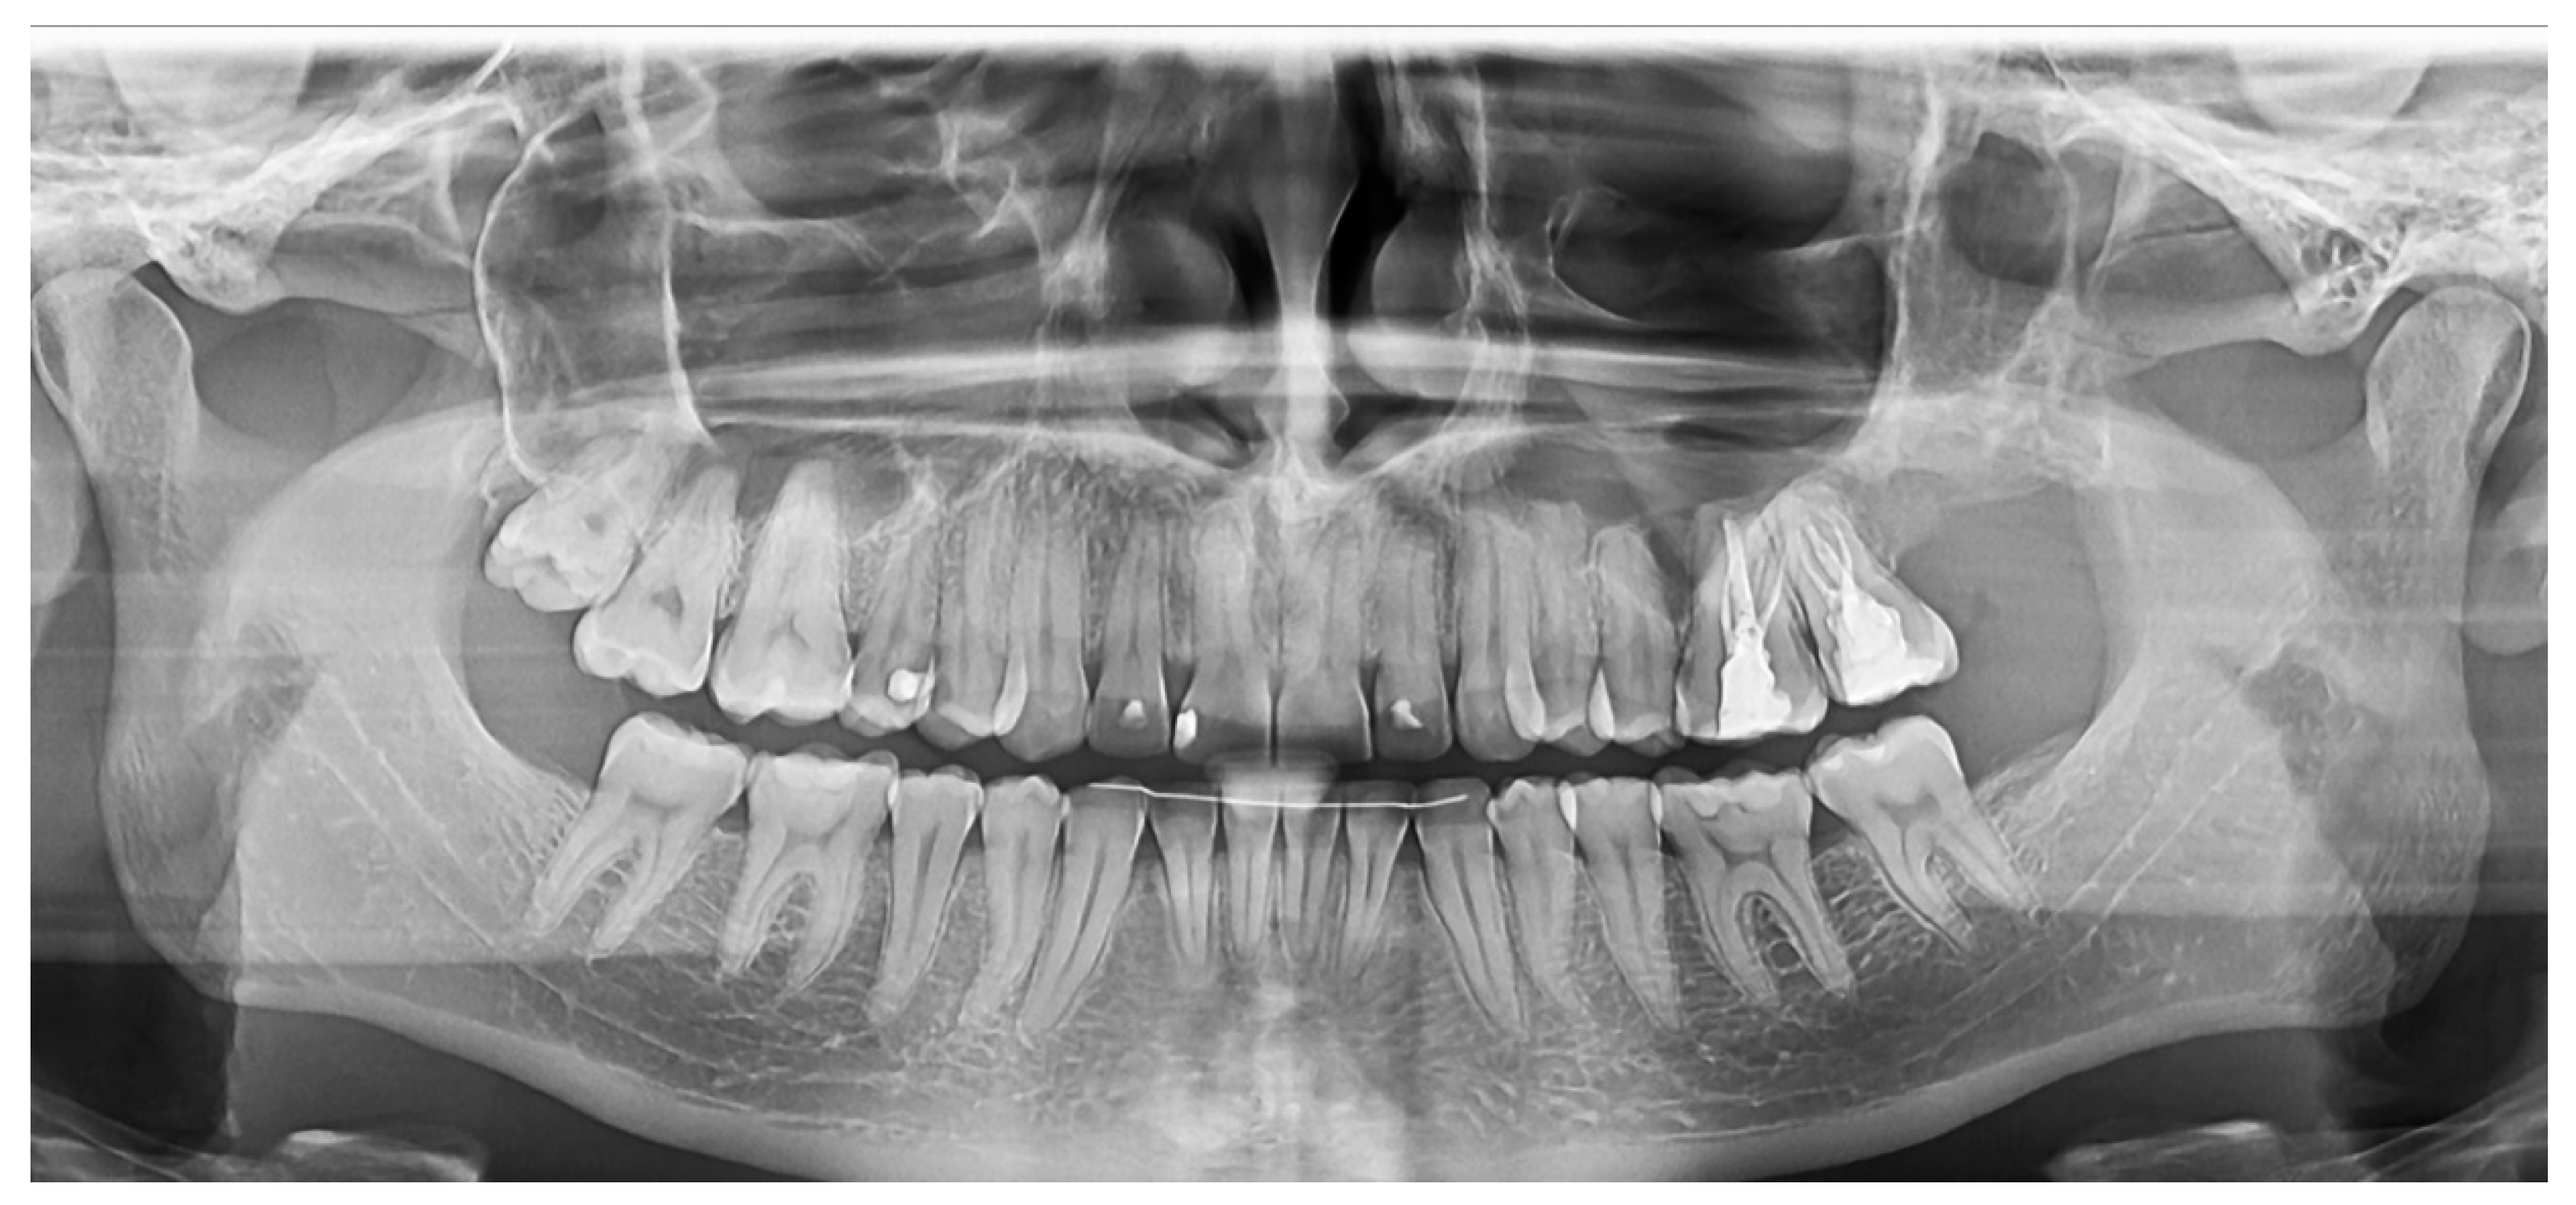

2.2.1. Case 1